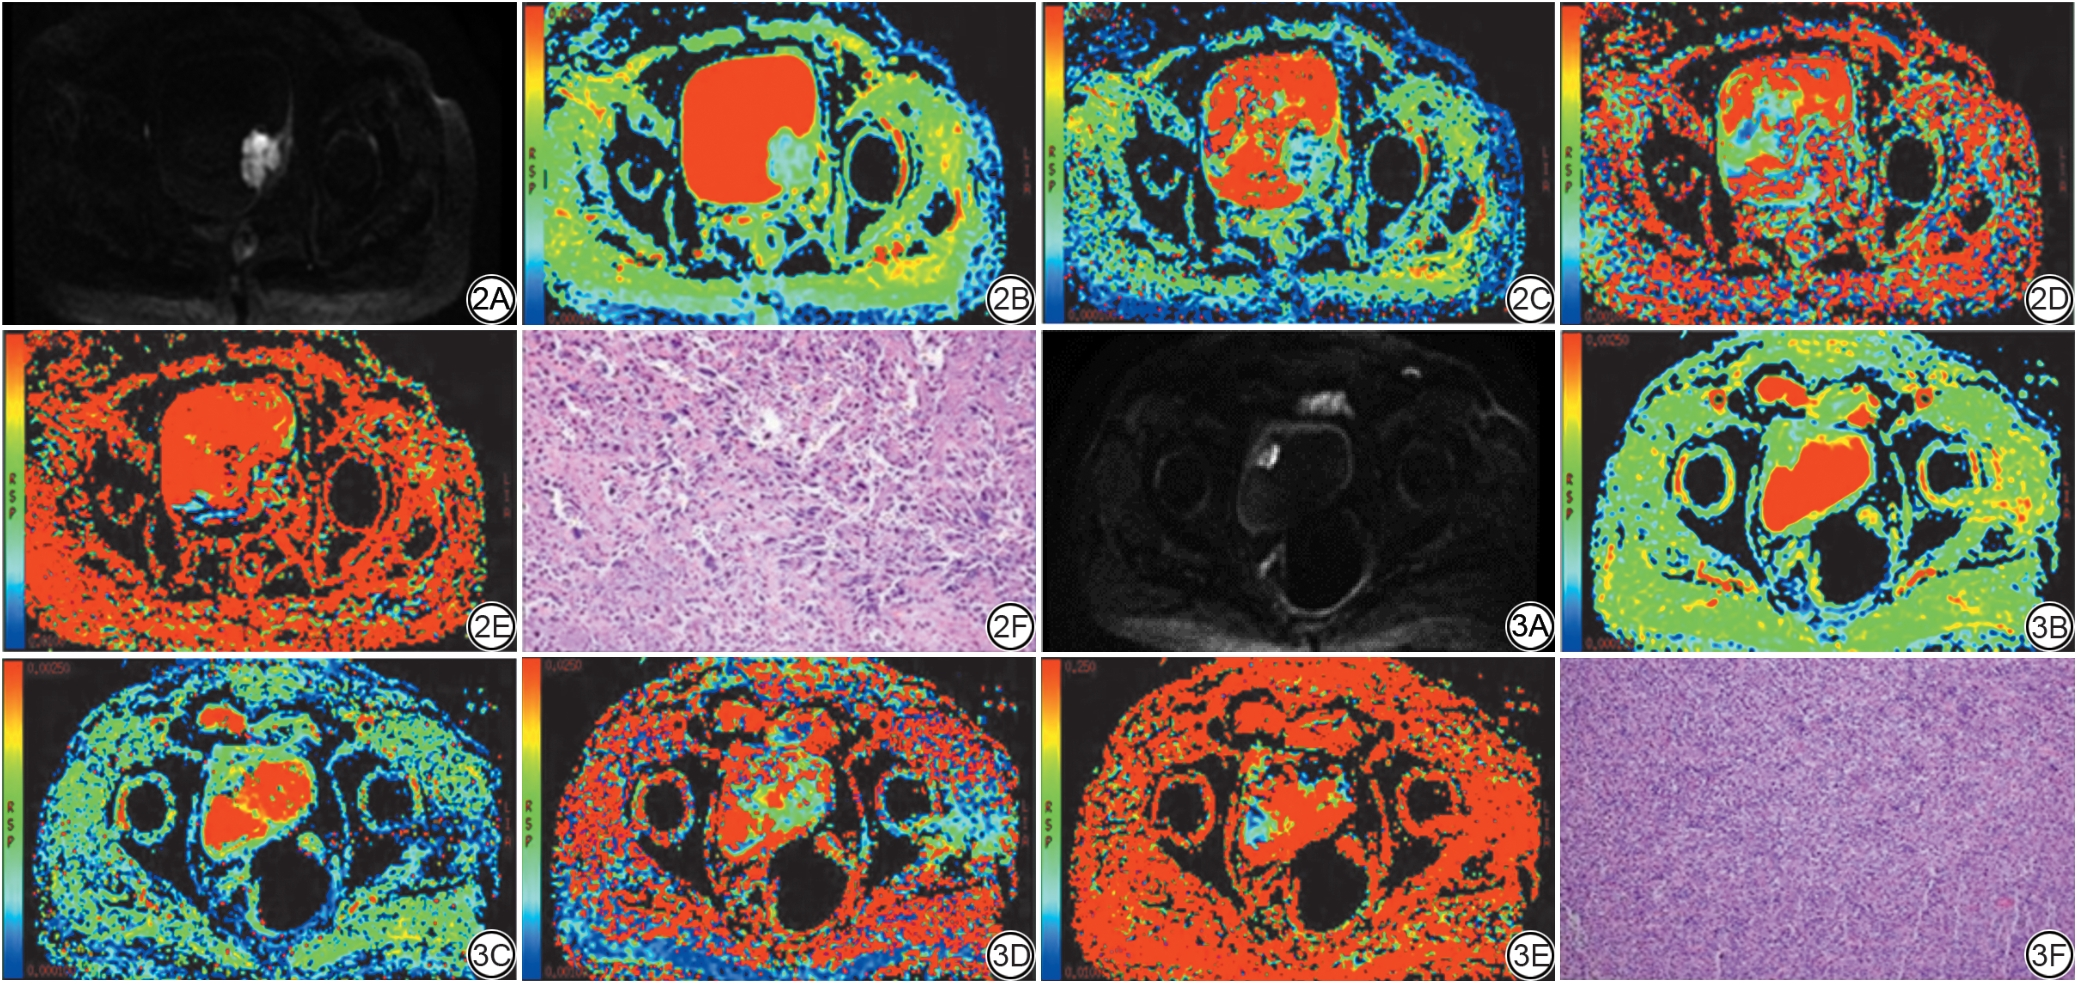

采用ADW 4.6后处理工作站中的mADC后处理软件进行图像后处理。分别由两名具有十年以上工作经验的放射科主治医师参考T2WI、DWI序列在IVIM-DWI图像上手动选取膀胱肿瘤ROI,在肿瘤显示的最大层面上进行,尽量避开肿瘤囊变、坏死、液化区域,避开膀胱壁,避开肿瘤与膀胱壁交界区域,并尽可能使ROI范围显示为最大,由一名具有三十年以上工作经验的放射科副主任医师解决相关争议问题并确定最终的ROI范围。每位患者的膀胱肿瘤病灶均选取3个ROI,通过mADC后处理软件分别得出图像分析数据:表观扩散系数(apparent diffusion coefficient, ADC)、真实扩散系数(D值)、灌注分数(f值)以及灌注相关扩散系数(D*值),对这3个ROI的ADC值、f值、D值、D*值分别取平均值。ROI勾画见图1

图1  感兴趣区勾画示意图。

Fig. 1  Schematic diagram of region of interest delineation.

两名医师测得的ADC、f、D、D*值具有良好的观察者间一致性,ICC分别为0.981、0.973、0.952、0.916;同一医师三次测量上述参数具有良好的观察者内一致性,ICC分别为0.991、0.976、0.989、0.971。结果显示,在高、低级别膀胱癌组中,低级别膀胱癌的ADC、f、D值均大于高级别膀胱癌,差异具有统计学意义(P<0.001),而D*差异无统计学意义;在MIBC、NMIBC组中,NMIBC的ADC、f、D值均大于MIBC,差异具有统计学意义(P<0.001),而D*差异无统计学意义。IVIM-DWI各参数值组间统计结果详见表2表3,典型病例IVIM-DWI、ADC、f、D、D*图像及病理结果见图2图3

图2  女,74岁,膀胱左后壁占位性病变。2A:IVIM-DWI(b=800 s/mm2)图像;2B~2E:分别为ADC(2B)、D(2C)、D*(2D)、f(2F)伪彩图;2F:术后病理(HE 10×10)示膀胱左侧壁浸润性尿路上皮癌,高级别,侵犯肌层、神经。

图3  男,73岁,膀胱右前壁占位性病变。3A:IVIM-DWI(b=800 s/mm2)图像;3B~3E:分别为ADC(3B)、D(3C)、D*(3D)、f(3F)伪彩图;3F:术后病理(HE 10×10)显示膀胱右前壁高级别尿路上皮癌,侵犯膀胱壁肌层。IVIM-DWI:体素内不相干运动扩散加权成像;ADC:表观扩散系数;D:真实扩散系数;D*:灌注相关扩散系数;f:灌注分数。

Fig. 2  Female, 74 years old, space occupying lesion of the left posterior wall of the bladder. 2A: IVIM-DWI image (b=800 s/mm2); 2B-2E: The pseudo-color graph of ADC (2B), D (2C), D* (2D), f (2E), respectively. 2F: Postoperative pathology (HE 10 × 10) shows invasive urothelial carcinoma of the left lateral wall of the bladder, of high grade, invading the muscular layer and nerves.

Fig. 3  Male, 73 years old, space occupying lesion of the right anterior wall of the bladder. 3A: IVIM-DWI image (b=800 s/mm2); 3B-3E: The pseudo-color graph of ADC (3B), D (3C), D* (3D), f (3E), respectively. 3F: Postoperative pathology (HE 10 × 10) shows high-grade urothelial carcinoma of the right anterior wall of the bladder, invading the muscular layer of the bladder wall. IVIM-DWI: intravoxel incoherent motion diffusion-weighted imaging; ADC: apparent diffusion coefficient; D: true diffusion coefficient; D*: perfusion-related diffusion coefficient; f: perfusion fraction